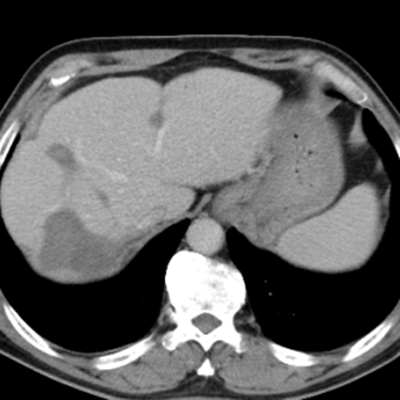

治療前:箭頭處均為轉(zhuǎn)移性腫瘤

治療后:未見(jiàn)明顯活性轉(zhuǎn)移腫瘤